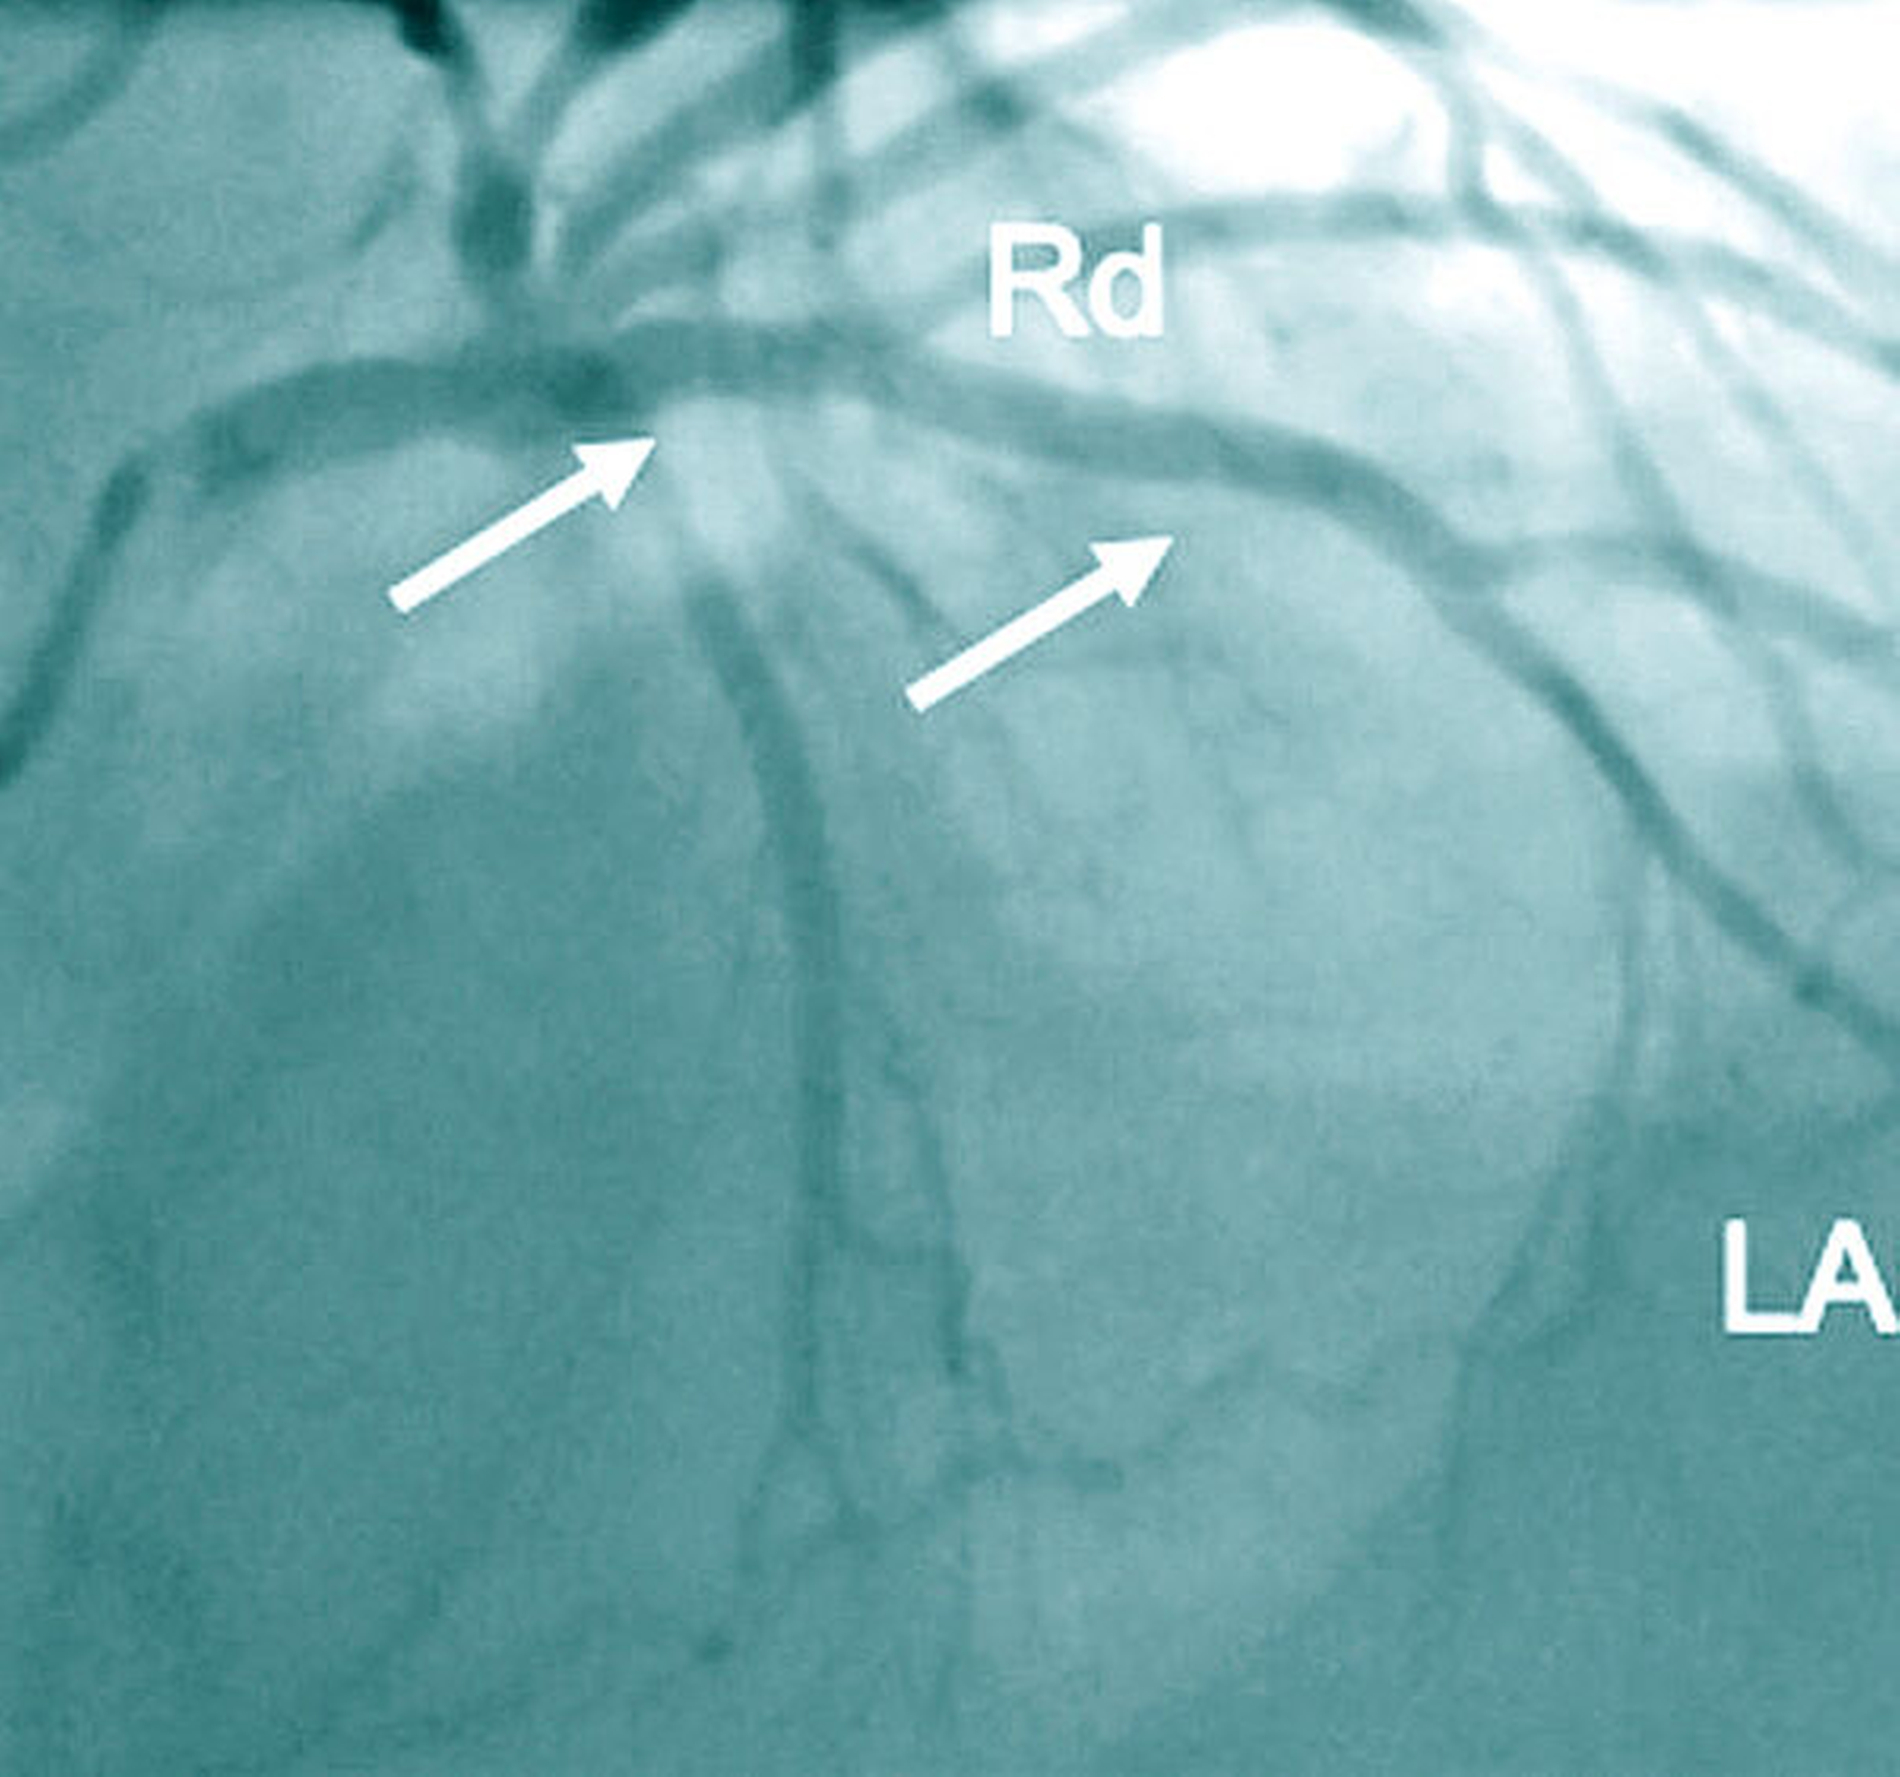

Die KHK ist gekennzeichnet durch arteriosklerotische Veränderungen der Herzkranzgefäße (Abbildung 1a). Die Folge kann eine verminderte Durchblutung und dadurch bedingte Schädigung der Herzmuskulatur sein. Klinische Korrelate für die gestörte Koronardurchblutung sind die Angina pectoris (Brustenge) und Herzrhythmusstörungen bis hin zum plötzlichen Herztod. Ein Herzinfarkt mit nachfolgender Herzinsuffizienz stellt eine bedeutsame Komplikation der KHK dar. Als Therapie kommen bei der Erkrankung der kleineren Gefäße Medikamente (Nitrate, Betarezeptorenblocker, Calcium-Kanal-Blocker) und bei Beteiligung der großen Koronargefäße bevorzugt die Dilatation/Stentversorgung im Rahmen einer interventionellen Therapie oder einer Operation (aortokoronare Bypass-Versorgung) in Betracht (Abbildungen 1b und 1c).